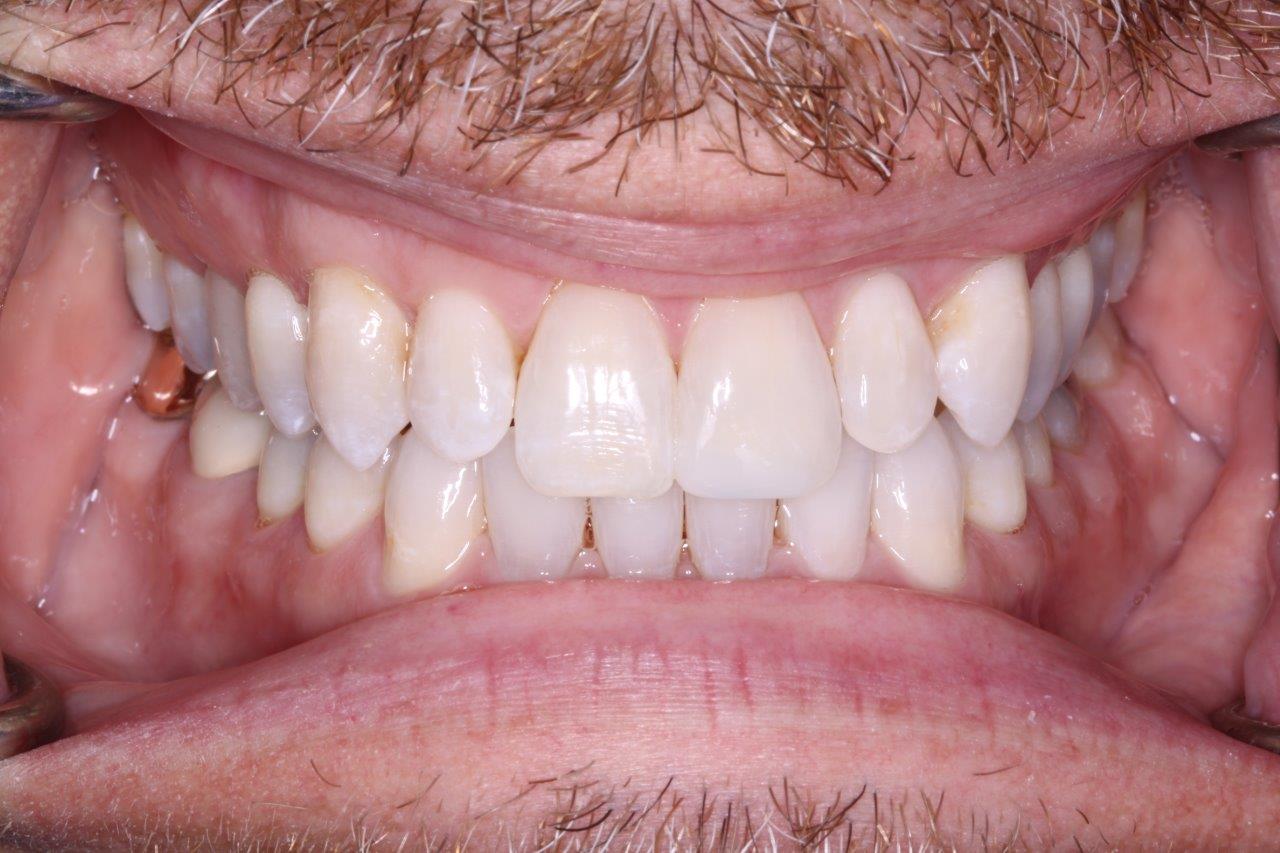

Crown & Veneer

After